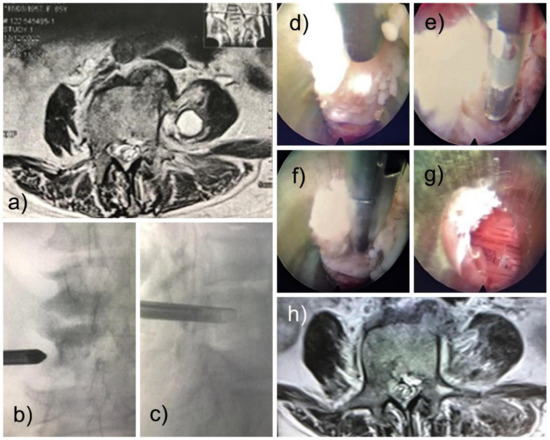

A 69-year-old female came in with back pain due to spondylodiscitis. She was treated with antibiotics for 90 days without improvement. Worsening symptoms included malaise, low back pain, and weakness in the lower limbs. She had paresis of the left lower limb with muscle strength grade 3/5 in the L4 innervated motor groups and grade 4/5 in the hip flexors. Computed tomography of the lumbar spine was performed, showing a low attenuation lesion in the left psoas. Percutaneous needle aspiration and medical treatment with vancomycin and ceftriaxone were attempted at another facility before the patient was admitted to our service for surgical debridement of her spinal infection. A new MRI scan of the lumbar spine with contrast showed an oval, homogeneous paravertebral lesion in the left psoas muscle below the L4 transverse process with hyperintensity on T2-weighted images (Figure 1a). The images suggested a differential diagnosis of abscess, granuloma, or fibrosis. Surgical debridement with the FED technique was proposed to the medical team, and the patient consented to it.

3. Surgical Technique and Recovery

Based on our experience and the location of the infection of the psoas fibrosis, we accessed the Transforaminal approach (also called the modified extraforaminal approach, MEA). The operation was performed with local anesthesia and sedation (MAC) with the patient in the prone position on a radiolucent table. A third-generation endoscope system (Vertebris Stenosis, RIWOspine GmbH, Knittlingen, Germany) was used. This oval endoscope measures 9.3 × 7.4 mm in outer diameter and has a 20° optical angle with a 5.6 mm diameter working channel and a 117 mm working length. An articulating radiofrequency probe (Elliquence, Baldwin, New York, NY, USA) was used for coagulation and tissue ablation. The MRI identified the lesion as anterior to the distal half of the left L4 transverse process (Figure 1b,c). The planning of the surgery was like a traditional transforaminal approach (MEA). After addressing the foramen and visualizing the characteristics of the disc without infection or pus, the endoscope was tilted to reach the tip of the transverse process under fluoroscopic guidance and direct video endoscopic visualization, and we found the psoas lesion. The lesion contained no pus but was composed of fibrotic and granulomatous tissue (Figure 1d–f). A delicate resection was performed, with subsequent visualization of the lesion-free muscles (Figure 1g). The outside-in approach was more convenient; in this case, the patient improved clinically with significantly less pain. The motor strength returned rapidly, and the patient could walk on the same day of surgery. Postoperatively, there was a transitory weakness of hip flexion, possibly due to psoas manipulation for lesion resection. It improved within six weeks. Oswestry’s disability index was less than 10, and VAS was 2. A postoperative surveillance MRI of the lumbar spine was performed. It demonstrated the complete removal of the infectious lesion (Figure 1h). The histopathological evaluation confirmed fibrotic tissue. Cultures from intraoperative specimens were negative for fungi, tuberculosis, and anaerobic and aerobic cultures, which were all negatives. Two months after the full endoscopic debridement, the patient was asymptomatic.

Figure 1. Shows a preoperative MRI scan of a 69-year-old female who initially presented back pain due to spondylodiscitis. The patient developed a psoas abscess shown as a round enhancing lesion on the T2-weighted axial MRI scan with intravenous contrast (a). The lesion was surgically treated with full endoscopic debridement (FED) with the working cannula placed in the center of the lesion below the left L4 transverse process (b,c). A fibrotic lesion was found intraoperatively (d,e), which was resected with the use of rongeurs (f) until the healthy red psoas muscle was visualized (g). A radiofrequency probe was used to achieve hemostasis. (h) A similar MRI scan was taken six weeks after the index FED confirmed the lesion’s successful removal. The patient recovered rapidly after surgery. The postoperative hip flexor weakness spontaneously resolved.